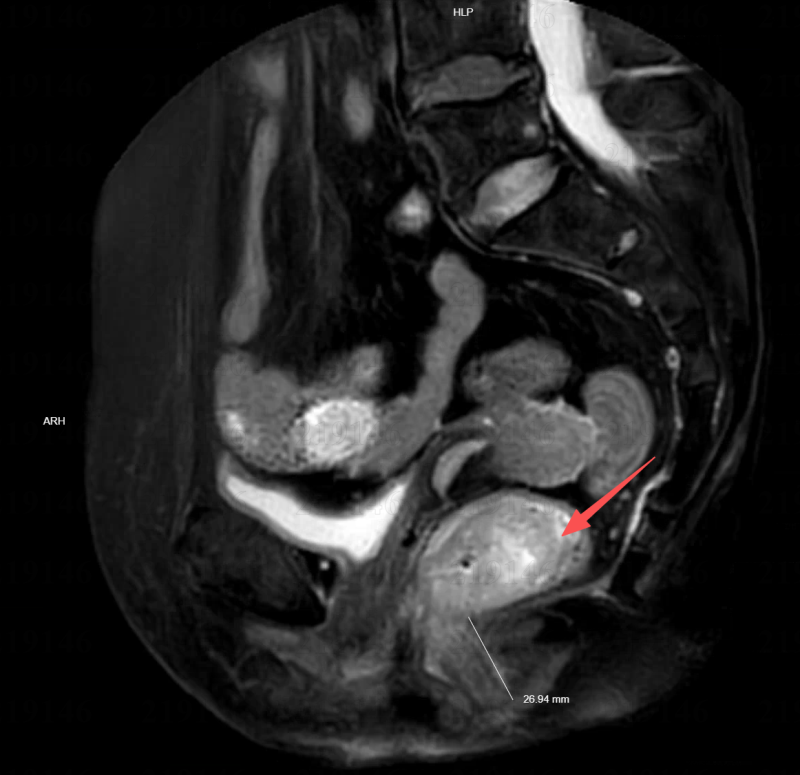

• 在医学发展的长河中,每一次技术的突破都意味着无数患者命运的改写。当直肠癌肿瘤逼近肛门仅剩约3厘米,许多患者面临的是“保命”与“保肛”之间的艰难抉择。然而,在温州医科大学附属第二医院(以下简称“温医大附二院”),来自江西的赵先生和陆女士,却在达芬奇机器人手术的辅助下,成功实现了肿瘤的完整切除与肛门的完美保留。这不仅是一场技术上的胜利,更是一次对生命尊严的守护。他们的故事,正是温医大附二院在低位直肠癌保肛领域不断探索与突破的生动写照。

直肠位于人体盆腔深处,空间狭小,血管与神经分布密集。当肿瘤生长在距离肛门较近的位置(医学上称为“低位或超低位直肠癌”),手术既要彻底切除肿瘤,达到根治效果,又要尽可能保留肛门功能,一直是结直肠外科领域的难题。许多患者因此陷入“保命”还是“保生活质量”的两难境地。

在赵先生和陆女士的案例中,温医大附二院组织了由肛肠外科、影像科、病理科、放疗科、麻醉科等多学科专家组成的MDT团队,进行了全面的术前评估,为每位患者量身定制了“个体化保肛方案”。该方案在严格遵循肿瘤根治原则的基础上,最大限度地考虑了功能保留与术后生活质量的提升。

最终,由肛肠外科王中林主任团队主导,为两位患者实施了达芬奇机器人辅助下的直肠癌根治术。手术过程中,主刀医生坐在控制台前,精准操控机械臂,在极有限的空间内游刃有余地完成了解剖、分离、止血、缝合等一系列高难度操作。肿瘤被完整切除,肠道成功吻合,肛门结构与功能得以完美保留。术后,两位患者恢复迅速,均在术后第七天顺利出院,重返正常生活。